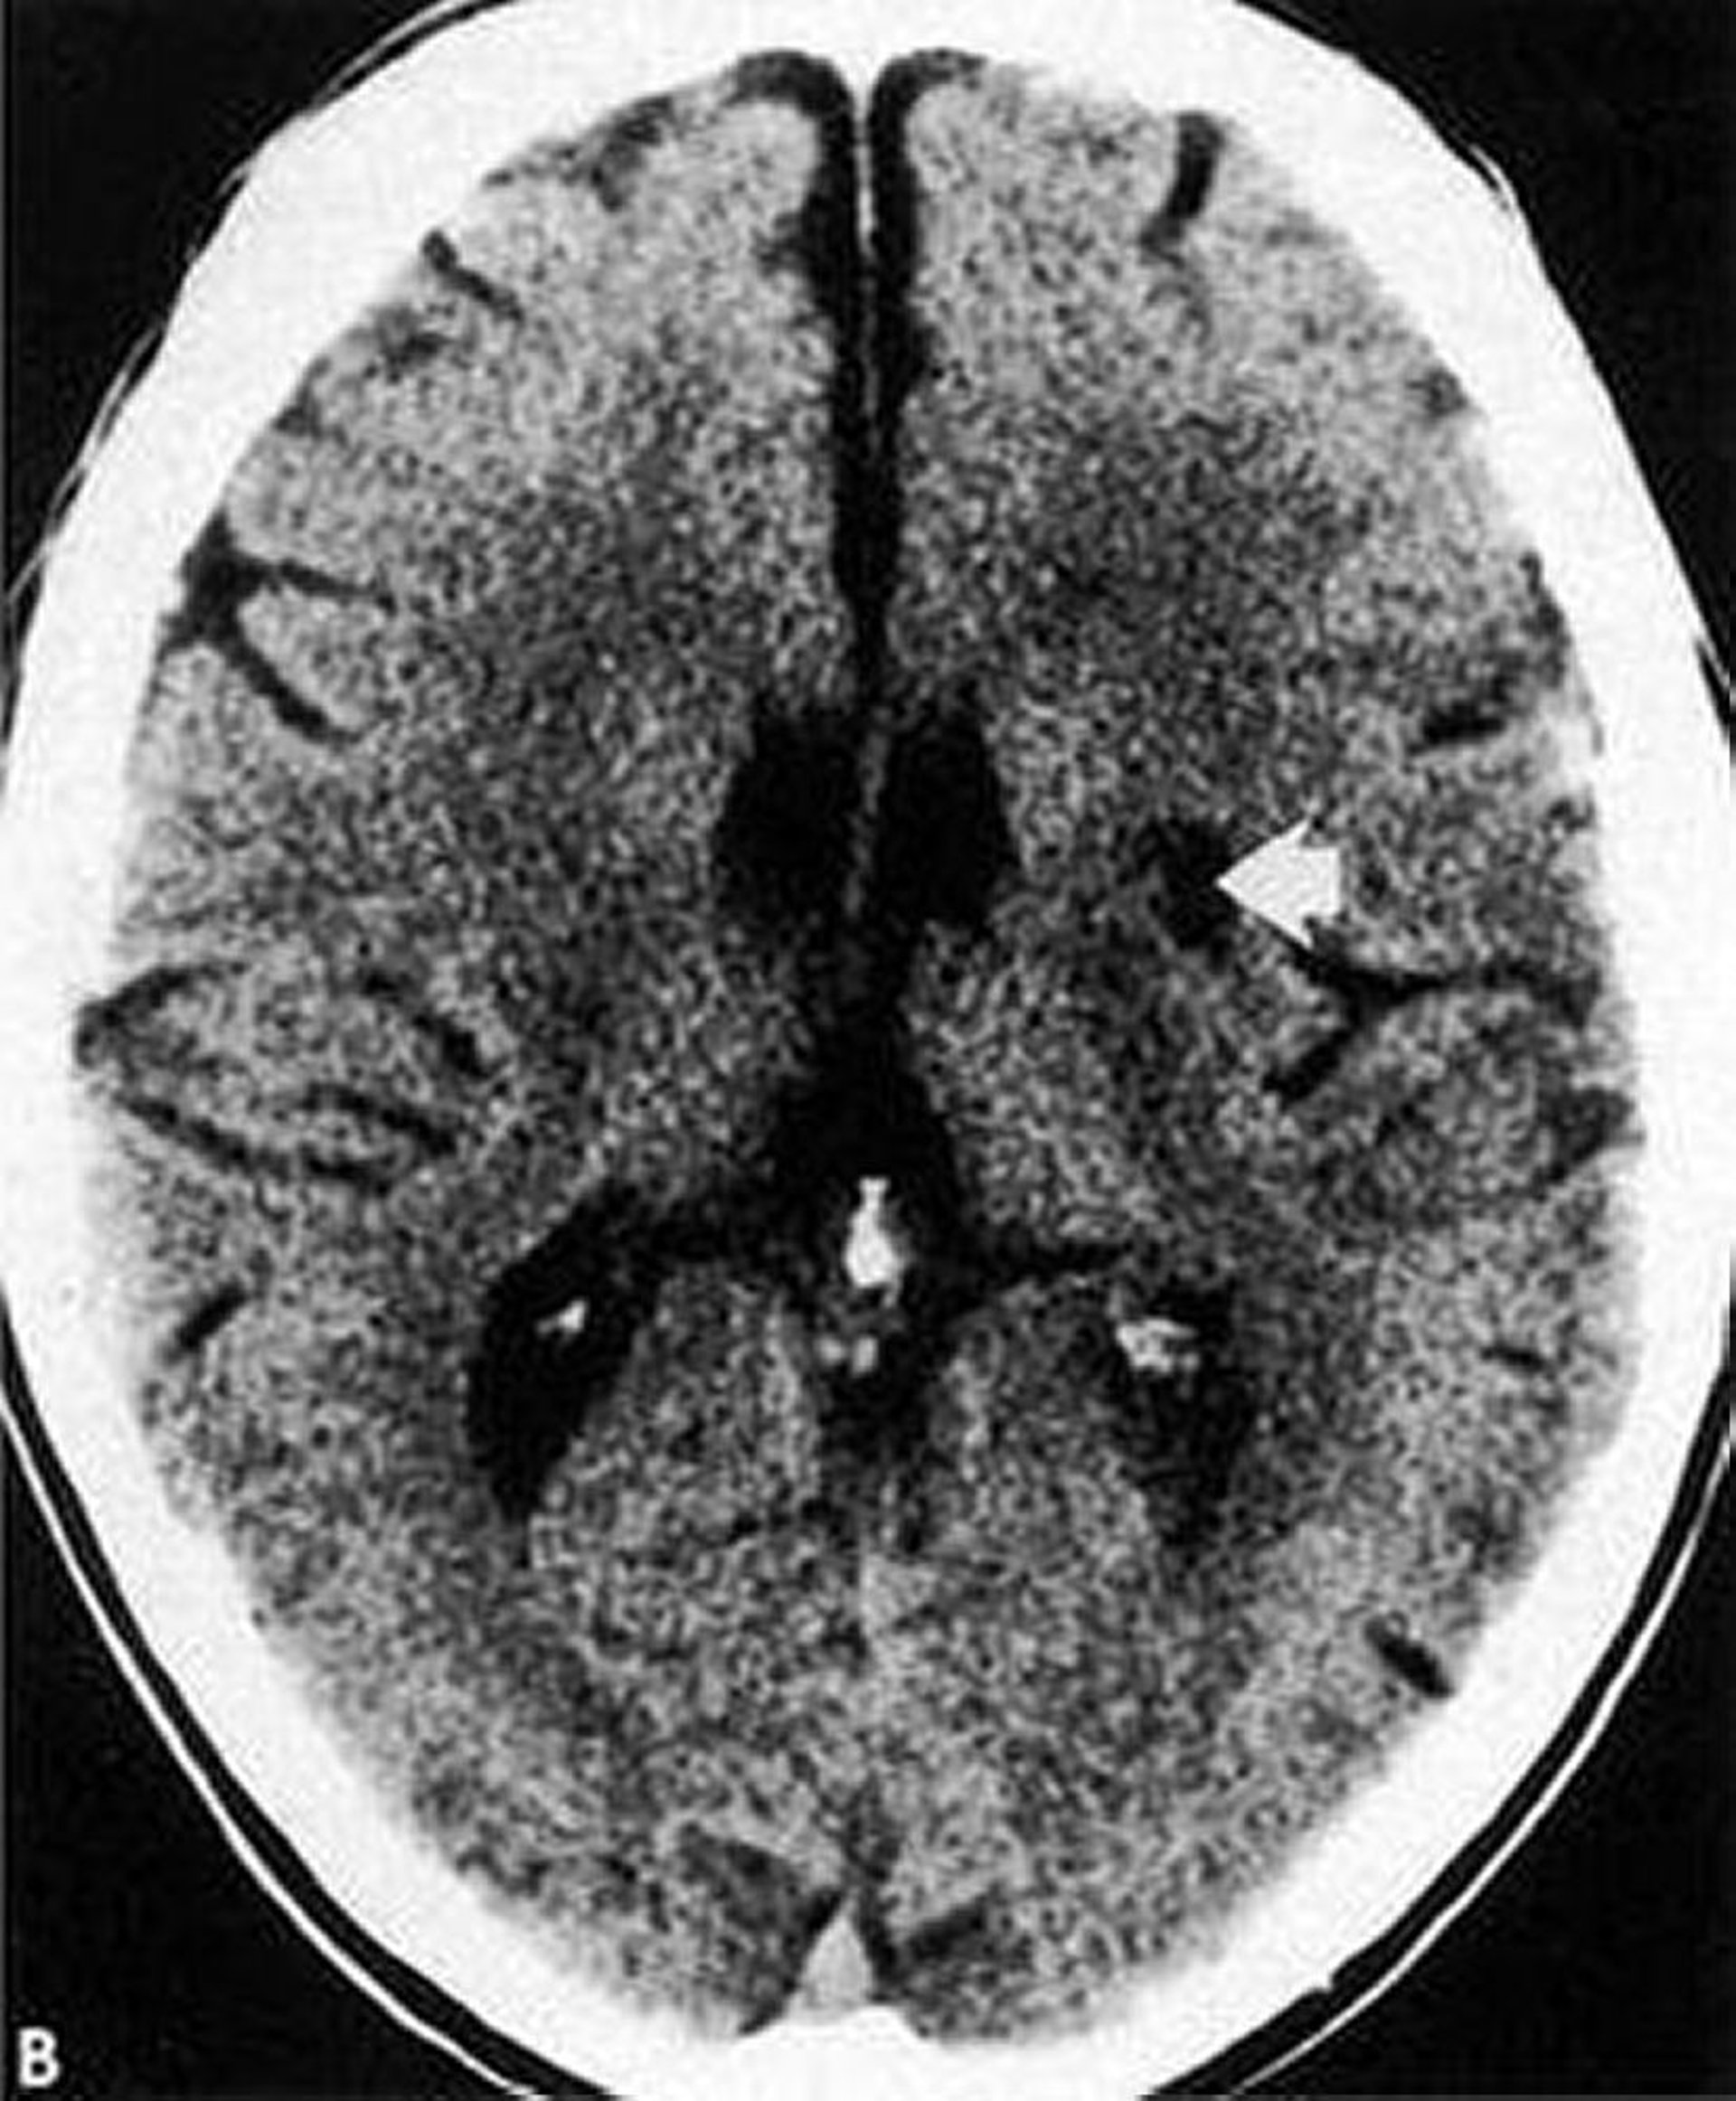

Infarctus lacunaire

Cette TDM montre un infarctus lacunaire de faible densité et bien défini (flèche) dans les noyaux gris centraux.

By permission of the publisher. From Geremia G, Greenlee W. In Atlas of Cerebrovascular Disease. Edited by PB Gorelick and MA Sloan. Philadelphia, Current Medicine, 1996.